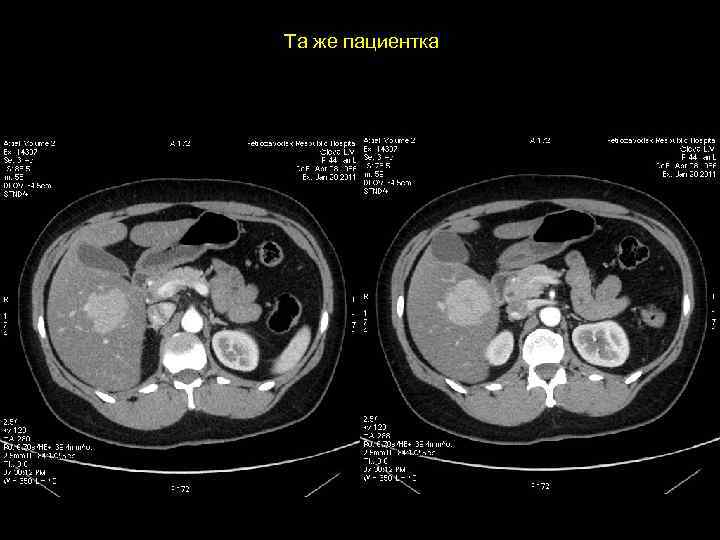

Та же пациентка

АКТУАЛЬНЫЕ ВОПРОСЫ РЕНТГЕНОЛОГИИ ЛУЧЕВАЯ ДИАГНОСТИКА ОЧАГОВЫХ ПОРАЖЕНИЙ ПЕЧЕНИ КАВЕРНОЗНАЯ ГЕМАНГИОМА Компьютерно-томографическая семиотика: - ограниченный участок пониженой плотности (до 50 -30 ед Н) - границы могут быть ровными, но нечеткими - после введения РКВ - характерный феномен усиления плотности от периферии к центру в течении нескольких минут после внутривенного введения РКВ